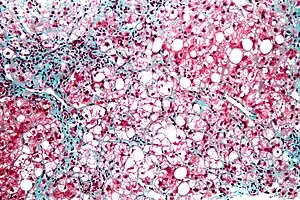

| Micrograph showing a fatty liver (macrovesicular steatosis), as seen in non-alcoholic fatty liver disease. Trichrome stain. | |

Fatty change represents the intracytoplasmatic accumulation of triglycerides (neutral fats). At the beginning, the hepatocytes present small fat vacuoles (liposomes) around the nucleus (microvesicular fatty change). In this stage, liver cells are filled with multiple fat droplets that do not displace the centrally located nucleus. In the late stages, the size of the vacuoles increases, pushing the nucleus to the periphery of the cell, giving characteristic signet ring appearance (macrovesicular fatty change). These vesicles are well-delineated and optically "empty" because fats dissolve during tissue processing. Large vacuoles may coalesce and produce fatty cysts, which are irreversible lesions. Macrovesicular steatosis is the most common form and is typically associated with alcohol, diabetes, obesity, and corticosteroids. Acute fatty liver of pregnancy and Reye's syndrome are examples of severe liver disease caused by microvesicular fatty change.[18] The diagnosis of steatosis is made when fat in the liver exceeds 5–10% by weight.[11][19][20]